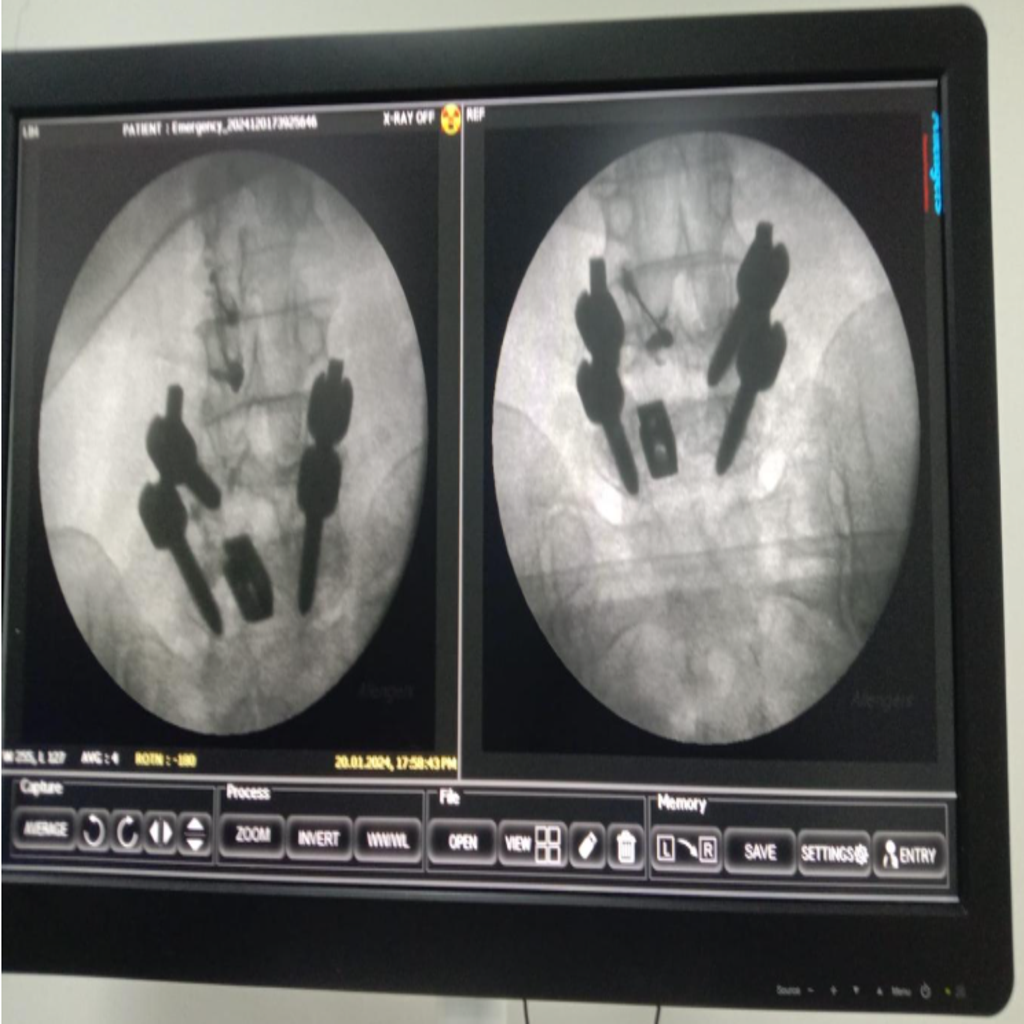

Fluoroscopy guided Intraarticular Facet joint Injection being carried out at Alleviate Pain Clinic, Bengaluru. Image Courtesy- Alleviate Pain Clinic

Image-guided precision treatments include:

- Lumbar facet joint injections for facet arthritis

- Medial branch blocks & radiofrequency ablation for chronic facet pain

- Sacroiliac joint injections for SI dysfunction

- Piriformis muscle injections (ultrasound-guided)

- Epidural or nerve root blocks for disc-related sciatica

These treatments:

- Target the exact pain generator

- Reduce medication dependence

- Avoid surgery in most cases